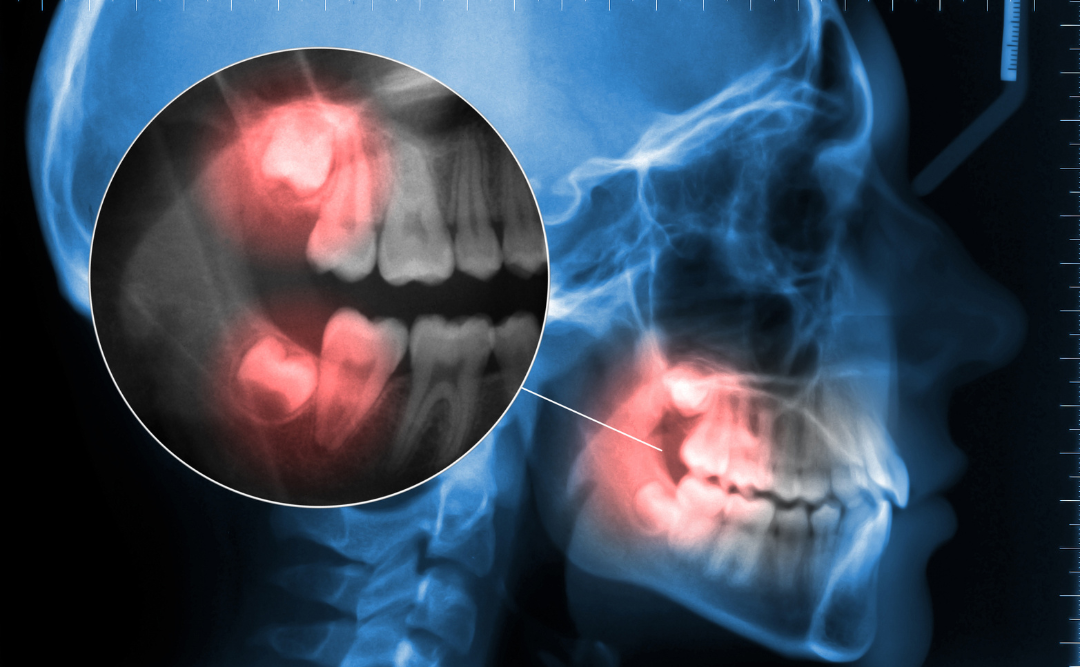

まずは検診でレントゲンを撮影し、親知らずの生え方や周りの歯に影響が出ていないかを確認します。

患者様の希望を踏まえ、親知らずを抜歯するか残しておくか治療方針を決めていきます。